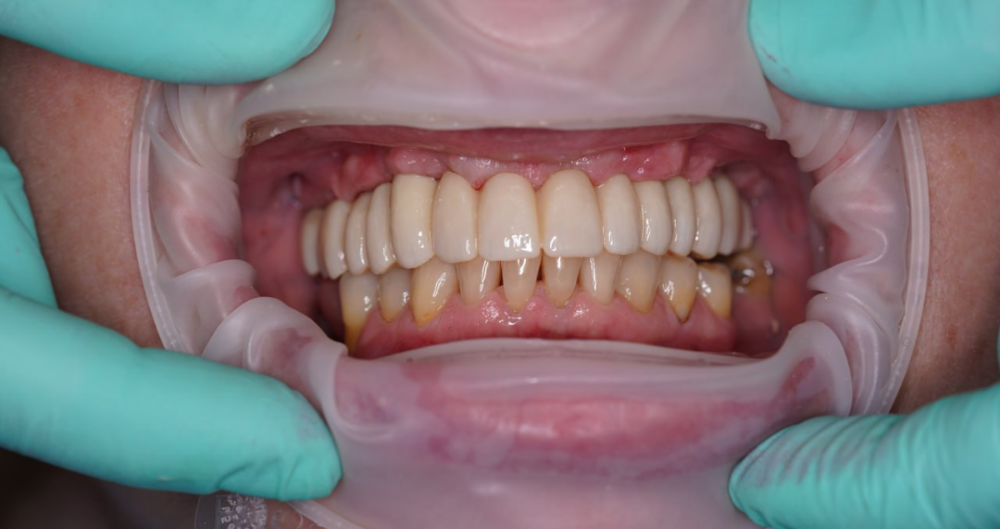

Technika All-on-X — I. fáze

Technika All-on-X — II. fáze

Ukázky práce před a po